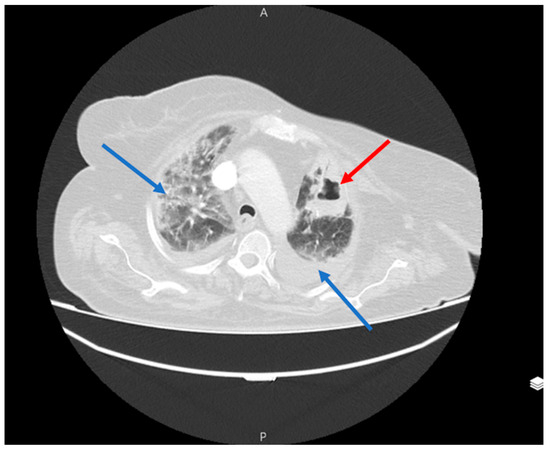

However, three weeks later, the patient developed shortness of breath symptoms with a dry cough and bilateral chest pain and was referred to the respiratory unit of the Valiasr Hospital in Zanjan, Iran. On admission, her SpO2 was 76%, her BP was 100/70 mmHg, her PR was 84/min, her RR was 21/min, and her T was 37.8 °C. Although her throat and nasal samples were negative for COVID-19, a non-contrast lung CT revealed typical COVID lung involvement with the presence of large septoid cavities in both the right and left lungs. In particular, a large cavity with an air-fluid level was observed in the left lower lobe, while a similar cavity was seen in the right upper lobe which extended to the middle and lower lobes (Figure 1 and Figure 2).

Figure 1.

Large septoid cavity in right upper lobe with the spread to the middle and lower lobes of the lung (red arrow).

Figure 2.

Large cavity with the air-fluid level in the left lower lobe (red arrow).